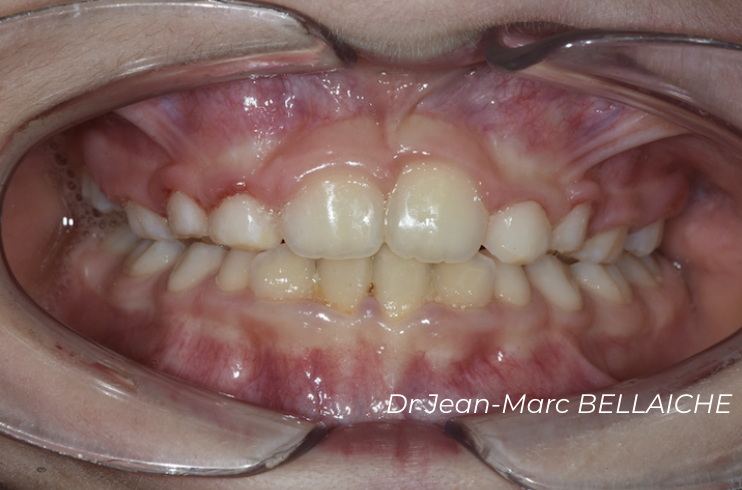

Cas 3 : Encombrement avec recouvrement incisif

Situation "Avant Traitement" : cas d'encombrement associé à un recouvrement excessif des incisives supérieures sur les inférieures.

Ce type de malocclusion peut nuire aux fonctions occlusales normales et peut être à l'origine de "déchaussements".